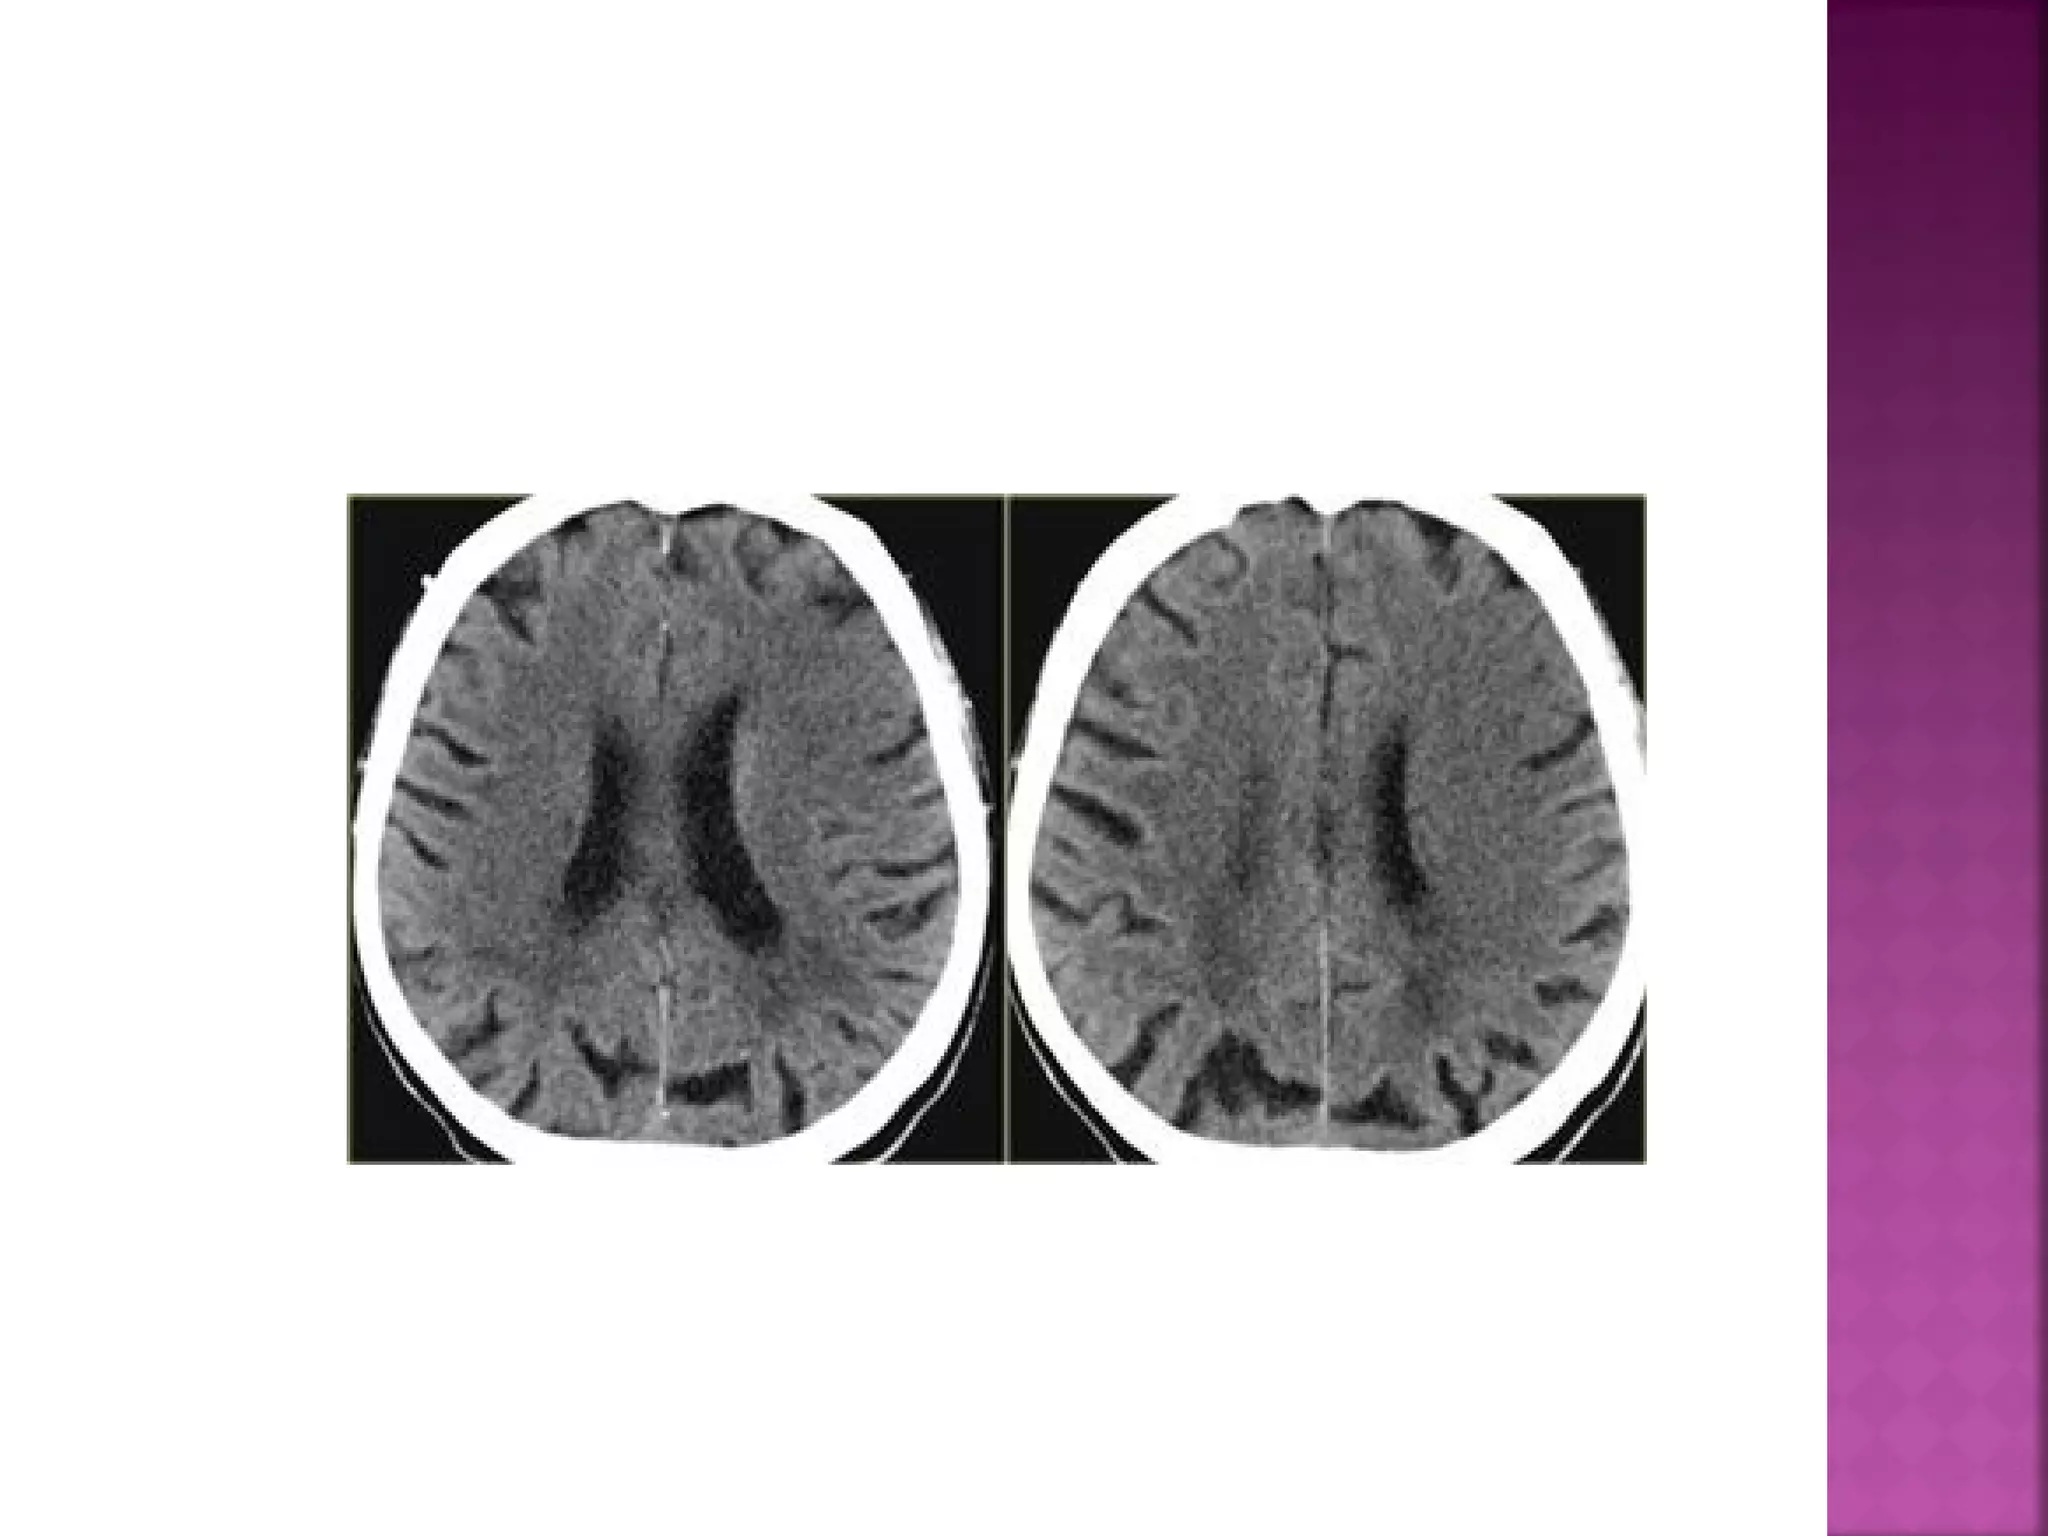

On CT 60% of infarcts are seen within 3-6 hrs

and virtually all are seen in 24 hours.

The diagnosis is infarction, because of the

location (vascular territory of the middle

cerebral artery (MCA) and because of the

involvement of gray and white matter, which

is also very typical for infarction.

 CT has theadvantage of being available 24 hours a day and is the gold standard for hemorrhage. Hemorrhage on MR images can be quite confusing. On CT 60% of infarcts are seen within 3-6 hrs and virtually all are seen in 24 hours.

 The diagnosis isinfarction, because of the location (vascular territory of the middle cerebral artery (MCA) and because of the involvement of gray and white matter, which is also very typical for infarction.